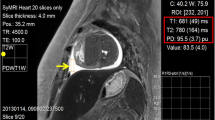

Three circular ROIs (size, 0.40–0.55 cm2) were placed each in the hematoma, in the underlying muscle tissue, and in the surrounding subcutaneous fatty tissue for the measurement of signal intensity (SI). Figure 1 illustrates the placement of the ROIs. The three measurements per tissue were averaged for further analysis. For each of the examination times, contrast coefficients according to Michelson [19] (CM = (SI1 − SI2) / |SI1 + SI2|) were calculated for the contrast between blood and fatty tissue and between blood and muscle tissue, respectively, using Matlab (2011b, TheMathworks Inc, Natick, MA, USA). It was investigated if the time course of the Michelson coefficient could be described by an unequivocal mathematical function.

Figure 2 shows a representative example of an artificial hematoma in all evaluated sequences and demonstrates good image quality. In all sequences, the SI of the fatty tissue and the muscle tissue remained relatively constant during the entire observation period, while the SI of the hematoma blood shows different time courses in the three sequences.

In the PDwSPAIR sequence, the SI of the hematoma was highly positive in comparison to the other tissues at the beginning of the measurements, and then subsequently decreased during the 2 weeks of examination. The difference of SI between blood and fatty tissue decreased over time (from 122.8–433.1 at the beginning to 37.0–230.5 after 7 days), but the hyperintensity of the hematoma versus fat is still well visible after 1 week. In the TIR sequence, the hematoma showed a negative contrast behavior versus muscle and fatty tissue, respectively, and after 7 days, the hematoma could scarcely be differentiated from the surrounding fatty tissue. In the MSE sequence, the hematoma was hypointense versus fatty tissue, and SI increased over time when averaged over all volunteers to reach almost the same SI as the subcutaneous fat after 2 weeks. Compared to muscle tissue, the artificial hematomas showed very high SI at the beginning, and with increasing time, the SI further increased while the SI of skeletal muscle was constant. The measured SI values for all volunteers are shown in detail in Table 2, whereas Table 3 gives a comprehensive overview on median and range of SI values directly post-injection and after 2 weeks. A qualitative description of the contrast of the artificial subcutaneous hematomas versus the surrounding tissues in the three sequences over time is given in Table 4.